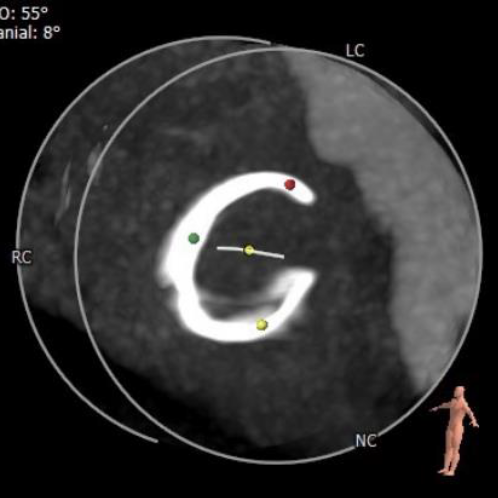

经详尽的影像学重建、评估,3D打印实物器械的模拟释放,心脏团队成员充分讨论后,决定采用经右侧颈静脉入路植入26mm规格Prizvalve®瓣膜。

CTA数据显示:患者三尖瓣位可见“C”型人工成形瓣环(28mm Edwards MC3),成形环内径22.3mm,有效开口面积381.1mm²。